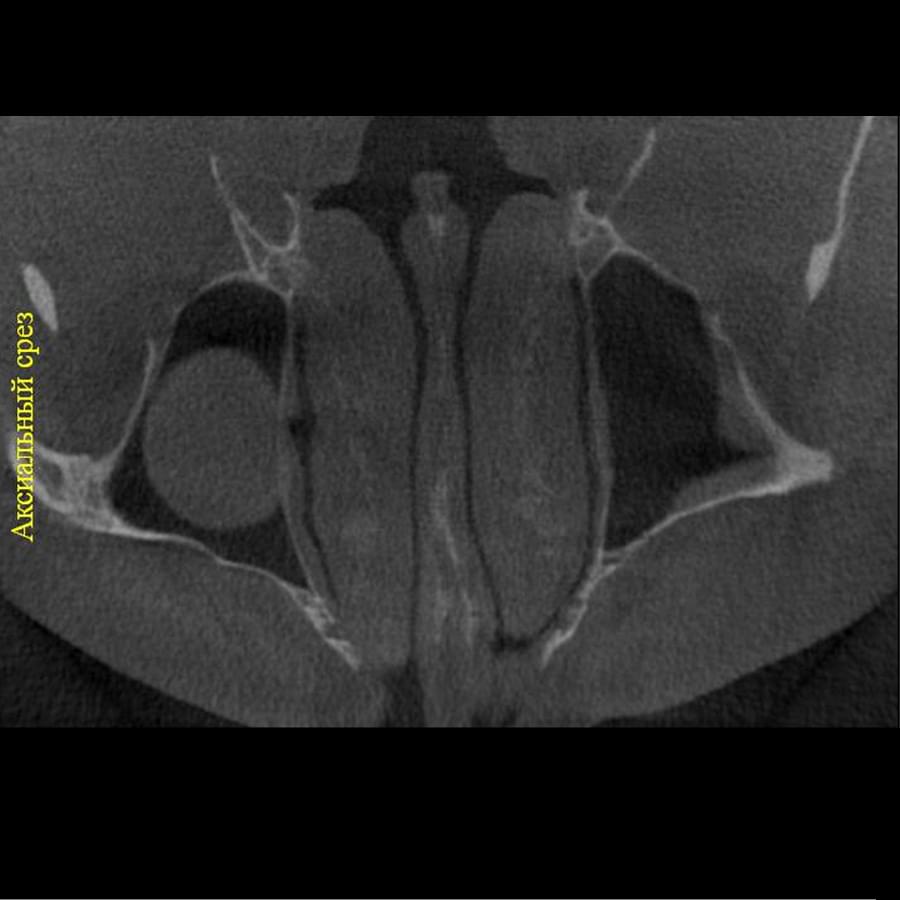

Комп'ютерна томографія

Щелепно-лицева діагностика

Мережа діагностичних центрів "МАЙРЕЙ ЛАБ" забезпечує точну та надійну діагностику

щелепно-лицевої ділянки з мінімальним ризиком для пацієнтів.

Ми використовуємо найсучасніше обладнання відомого виробника PLANMECA, що дозволяє отримувати високоякісні зображення за короткий час. Крім того, ми маємо власний сервер, на якому створюємо окрему скриньку для кожного лікаря, що забезпечує максимальну зручність та ефективність роботи.

3D цефалометричний аналіз є сучасною технологією, яка дозволяє отримувати точніші,

комплексніші та надійніші дані про зубну та скелетну структуру. Ця технологія може стати

великим кроком в перед для ортодонтів, які хочуть забезпечити найкраще можливе лікування

своїх пацієнтів.

Основні переваги 3D цефалометричного аналізу:

Точність: 3D цефалометричний аналіз забезпечує точніше визначення розмірів та відстаней між

зубами та кістковими структурами.

Комплексність: ця технологія дозволяє отримувати детальні дані про різні структури, такі як

кістка та м'язи, що дозволяє ортодонтам докладніше досліджувати деякі патології та планувати

лікування.

Надійність: 3D цефалометричний аналіз дозволяє отримувати надійніші результати, оскільки

виключає можливість помилок, пов'язаних зі спотворенням або перекриттям зображень.